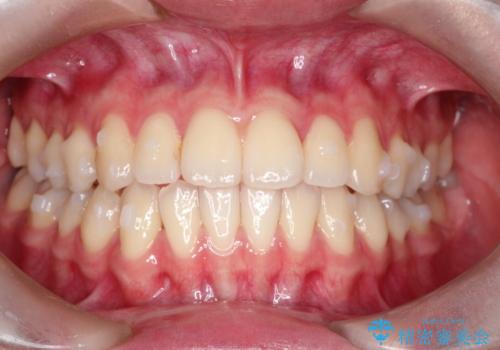

インビザラインによる非抜歯矯正 ガタガタな歯並びを整った歯並びへ

- 前歯のガタガタを主訴に来院されました。

抜歯矯正も考えられる状態でしたが、非抜歯矯正を希望されました。

使用時間を守っていただけたので、スムーズに治療を終わることができました。